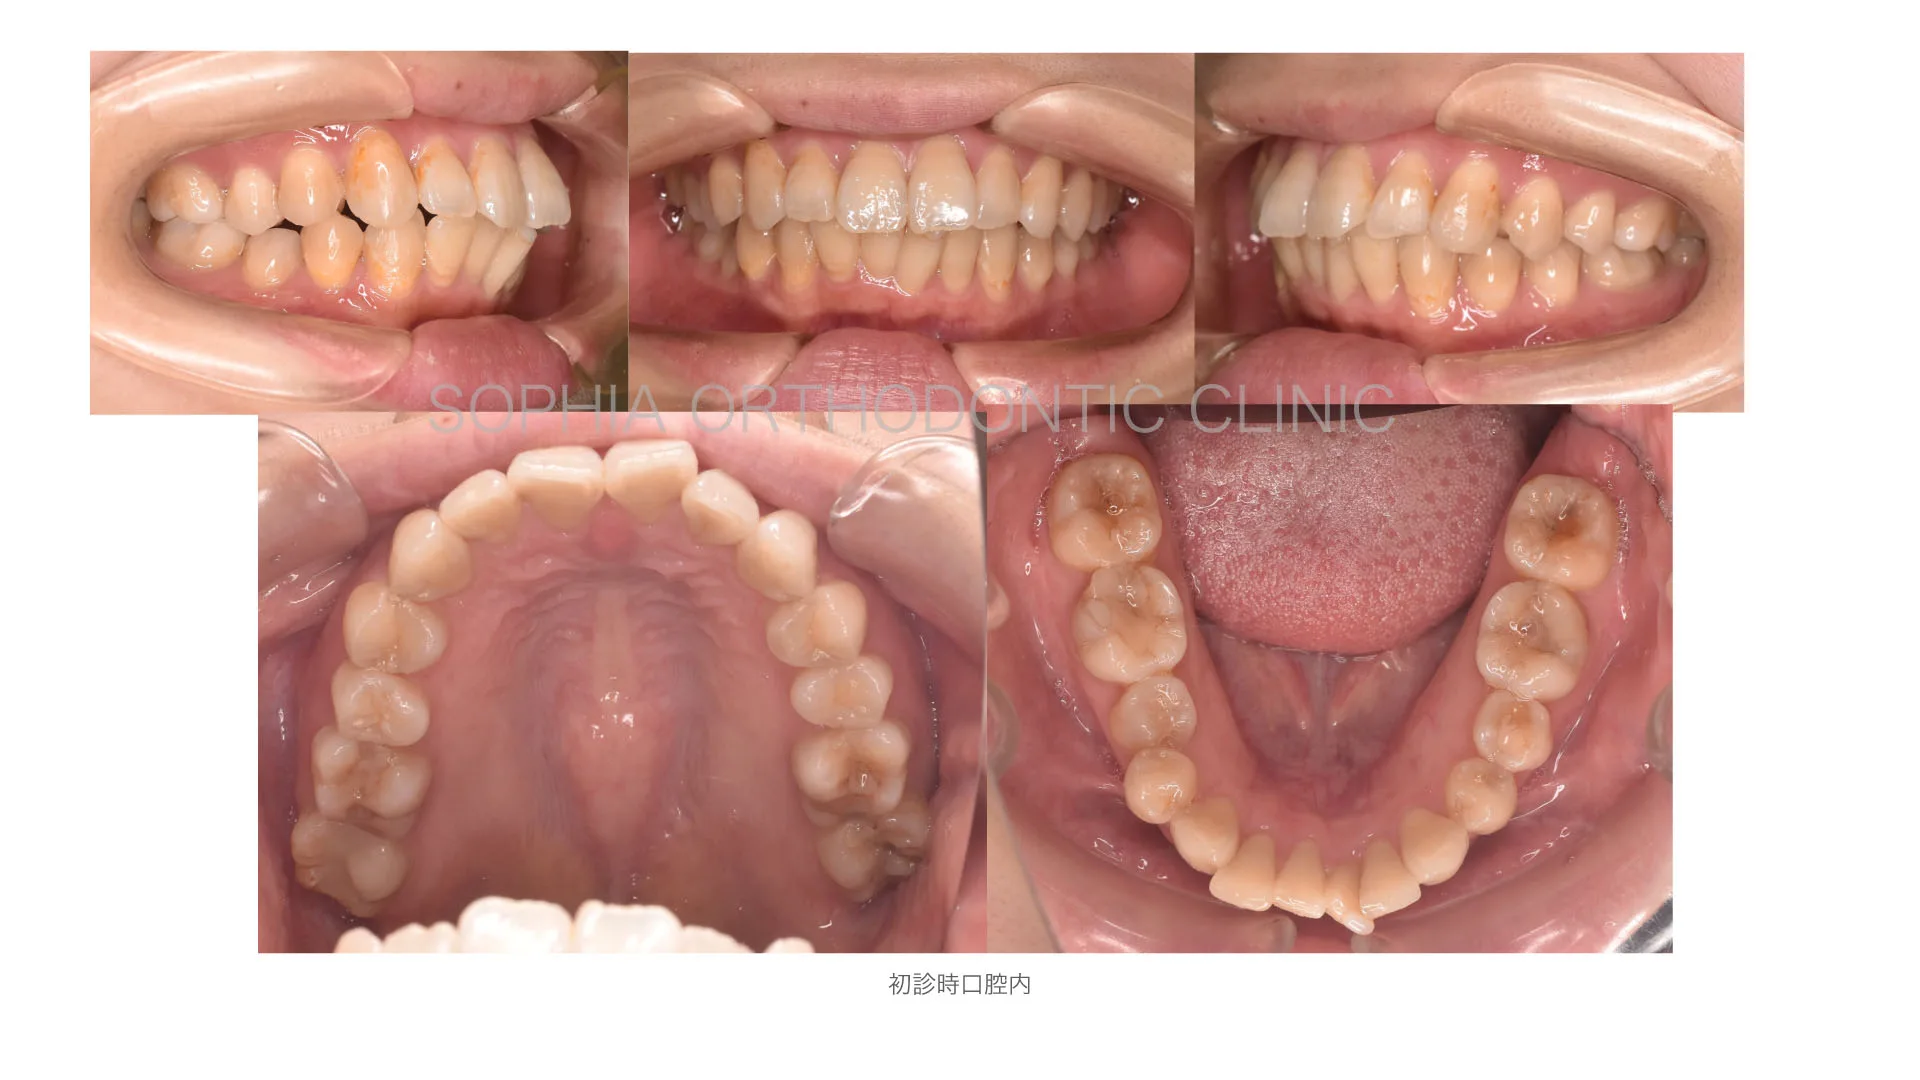

症例 前突